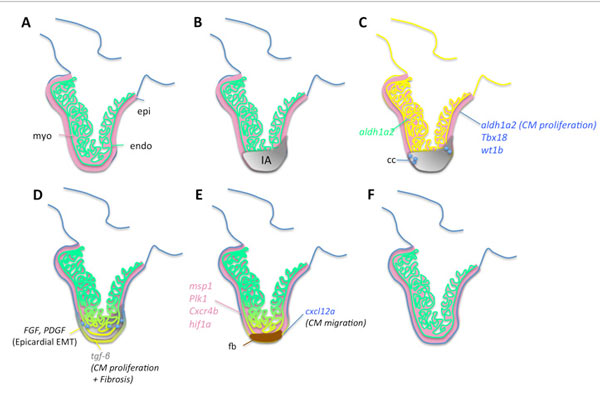

কোষ, কলার রিজেনারেশনের পথগুলি...

জেব্রাফিশের হার্টের কোষ, কলার রিজেনারেশনের ধাপগুলি

রিজেনারেশনের ধাপ (জেব্রাফিশ, ইঁদুর, মানুষ)